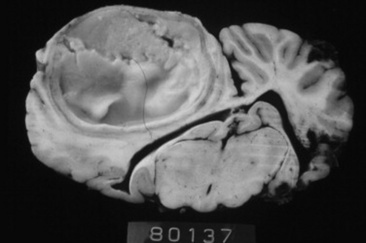

Cryptococcosis

Cryptococcosis is caused by C. neoformans (var. neoformans and var. gattii) and is a ubiquitous, saprophytic, round, basidiomycetous yeastlike fungus with a large heteropolysaccharide capsule that does not take up common cytologic stains (see Table 31-5, Fig. 31-20). The capsule forms a clear halo when stained with India ink. The capsule is immunosuppressive and antiphagocytic. A relatively high frequency of equine cryptococcosis occurs in Western Australia.311 There is an epidemiologic relationship between C. neoformans var. gattii and the Australian river redgum tree (Eucalyptus camaldulensis), whereas C. neoformans var. neoformans has historically been associated with bird (particularly pigeon) excreta.311 Cytologic or histopathologic identification is very reliable for diagnosis because of the characteristic morphology.361 Serologic testing with latex agglutination to identify cryptococcal capsular antigen is useful with resolution of lesions correlated with declining serum titers.331

image

Fig. 31-20 Photomicrographs of an impression smear from a biopsy of a mass in the nasal passage of a horse. The smear is extremely cellular, with abundant neutrophils and macrophages. Round yeast cells with large nonstaining capsules and occasional narrow-based budding consistent with cryptococcal organisms (arrow) are shown. (Modified Wright stain ×100.)

Courtesy Elizabeth Welles, Auburn University, Auburn, Ala.

Cryptococcosis in horses is associated primarily with pneumonia, rhinitis (Fig. 31-21), meningitis, and abortion. Successful medical treatment, however, has been reported rarely. Surgical removal of a localized jejunal lesion was successful in one horse.362 A pony with multiple pulmonary cryptococcomas, from which Cryptococcus gattii was cultured from both transtracheal washings and lung mass aspirates, was treated successfully with daily infusions of amphotericin B over 1 month. One year after cessation of treatment, clinical signs had resolved and the cryptococcal antigen titer had decreased from 4096 to 256.331

Cryptococcus should be treated with amphotericin B, fluconazole, or voriconazole (see Table 31-7).